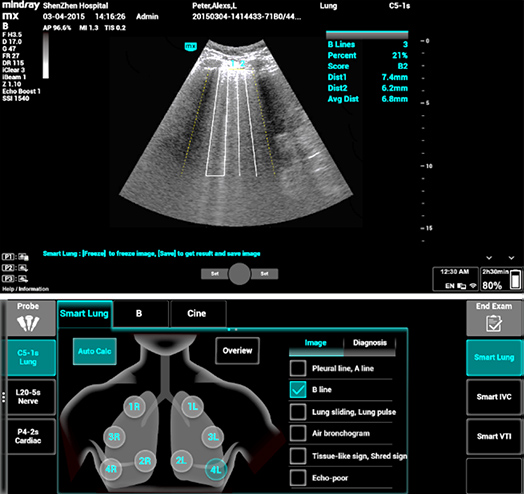

1Smart B-line

Le Smart B-line calcule automatiquement le nombre de lignes B et le pourcentage de zones de lignes B en accord avec le protocole sÃĐlectionnÃĐ pour une ÃĐvaluation rapide du tissu pulmonaire. Un schÃĐma global des poumons et un codage couleur du score pulmonaire permettent une ÃĐvaluation simple de la fonction pulmonaire.